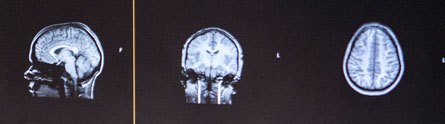

The IMAGEN Study recruited the teenagers at 14. Now, at 18, the same volunteers are back to see how their brains have changed over the last four years. The aim is to investigate factors that lead to the emergence of mental health issues such as mood disorders and substance abuse in adolescents.

The study, the first major study of its kind, is being led by Penny Gowland, a Professor of Physics at The University of Nottingham and Tomas Paus, a Professor of Psychology and Psychiatry at the University of Toronto. It is using genetics, brain imaging, psychological tests and interviews to get a better idea of how the teenage mind works.

Among the volunteers is 18 year old Sian Doherty from Nottingham. Back for the second stage of the study she said: “A lot of the questionnaires are about your life and the things you’ve been through. It has made me realise that I have had a normal life, nothing has happened to me that has influenced me in a bad way. I also have a CD of pictures of my brain!”